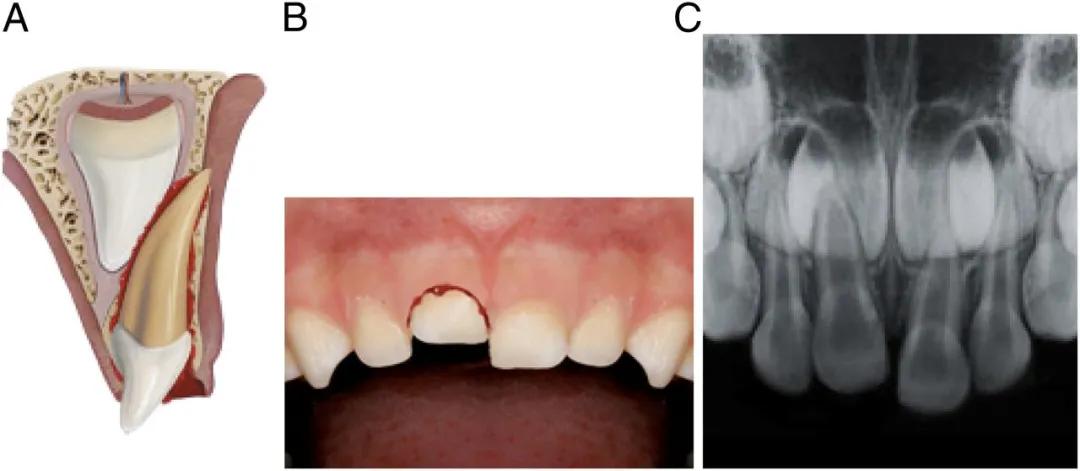

如果牙齿断得比较靠近牙根,或者摔裂了,裂缝延伸到牙根,这些情况可能会伤到牙神经,处理起来复杂一些。

图注:断牙暴露牙神经; 图源:AAP

为了防止牙神经感染,牙医通常采用一些材料,覆盖到这个露出神经的表面,然后再用材料把牙齿外形严密封闭。

如果牙齿磕断时间较长,露出的牙神经比较多,就采取牙髓切断术把受感染的这一部分牙神经去掉,把健康的牙髓保留下来,让牙根继续生长和发育。